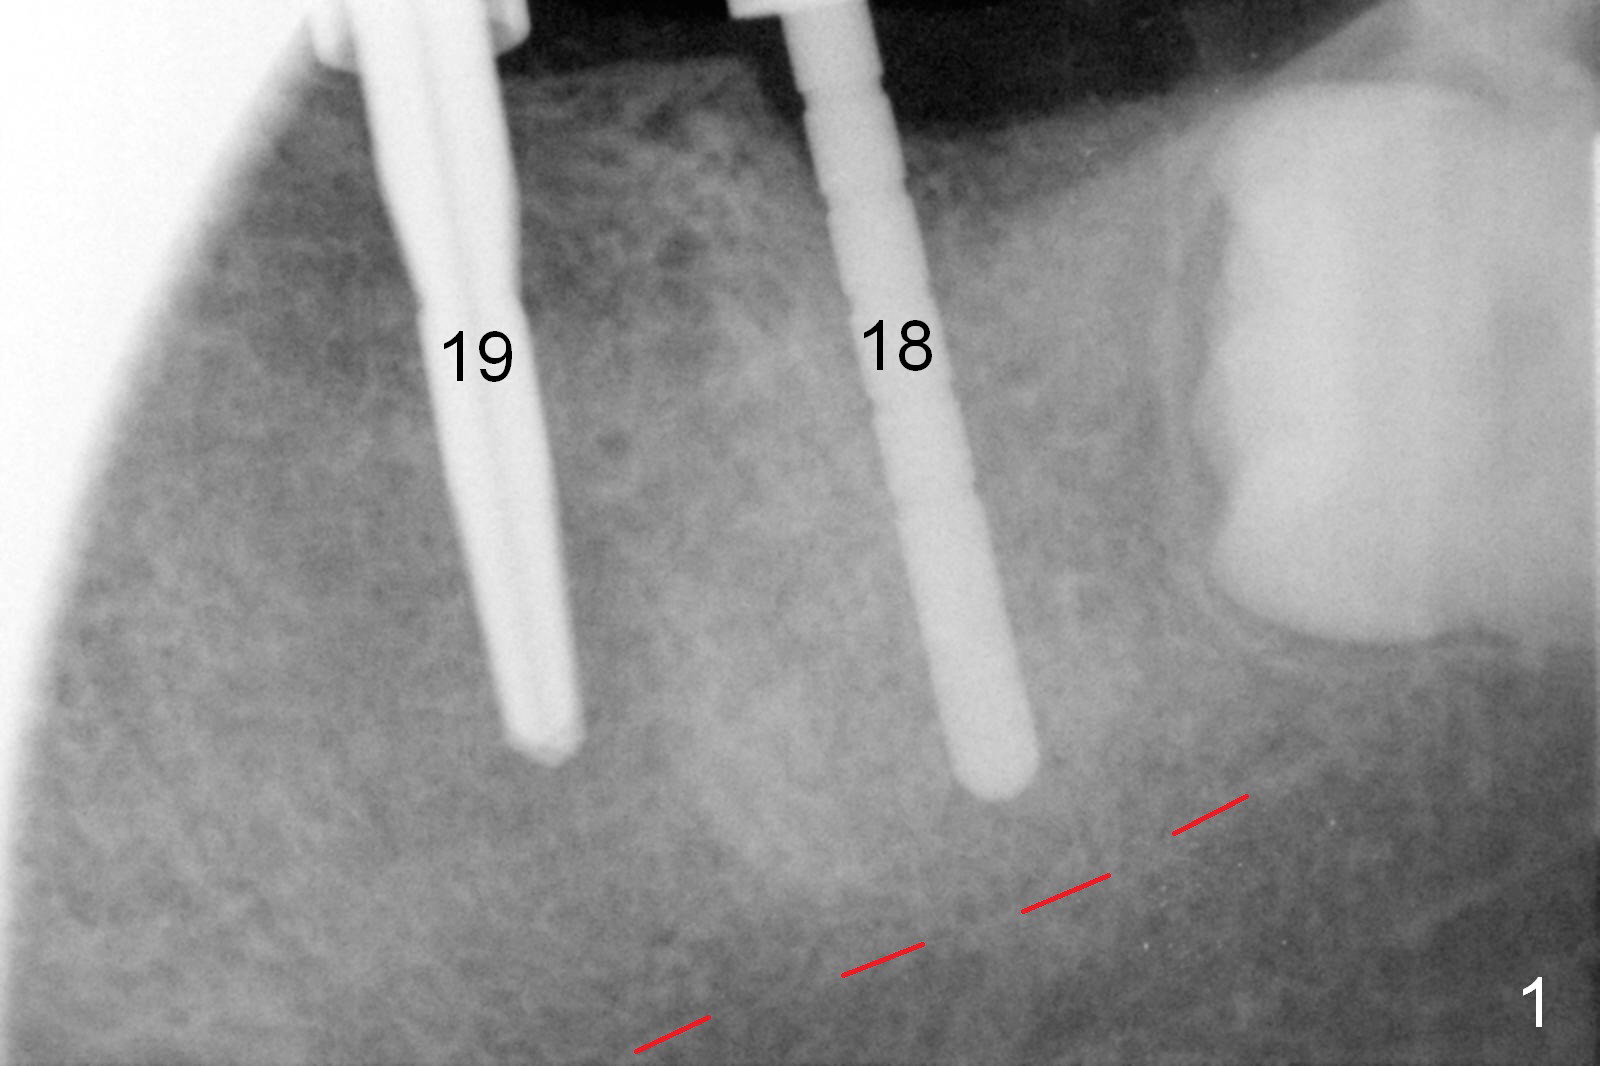

Infiltration anesthesia is enough for initial osteotomy at the site of #19 (Fig.1), but not for sectioning the tooth #18.  Block anesthesia has to be administered.  Fortunately it is safe to start osteotomy at #18 (~ 3 mm beyond the socket bottom, Fig.1 (red dashed line: the superior border of the Inferior Alveolar Canal (IAC))).  A 4.5x14 mm implant is stable at #19, while a 5x12 mm one at #18 is not (Fig.2).  Unfortunately bone graft has been placed.  When the implant is removed, a 4.5x14 mm drill is used to deepen the osteotomy for 2 mm.  The patient reports mild discomfort later on.  Hemorrhage occurs, which is stopped when the same implant is re-placed.  There is no stability.  The implant is removed (Fig.3,4).  More bone graft is placed, followed by collagen plug.  It appears that bone graft has been pushed into the IAC (Fig.4 arrowheads). Medro dose pak is prescribed.  In fact, no paresthesia is reported postop.